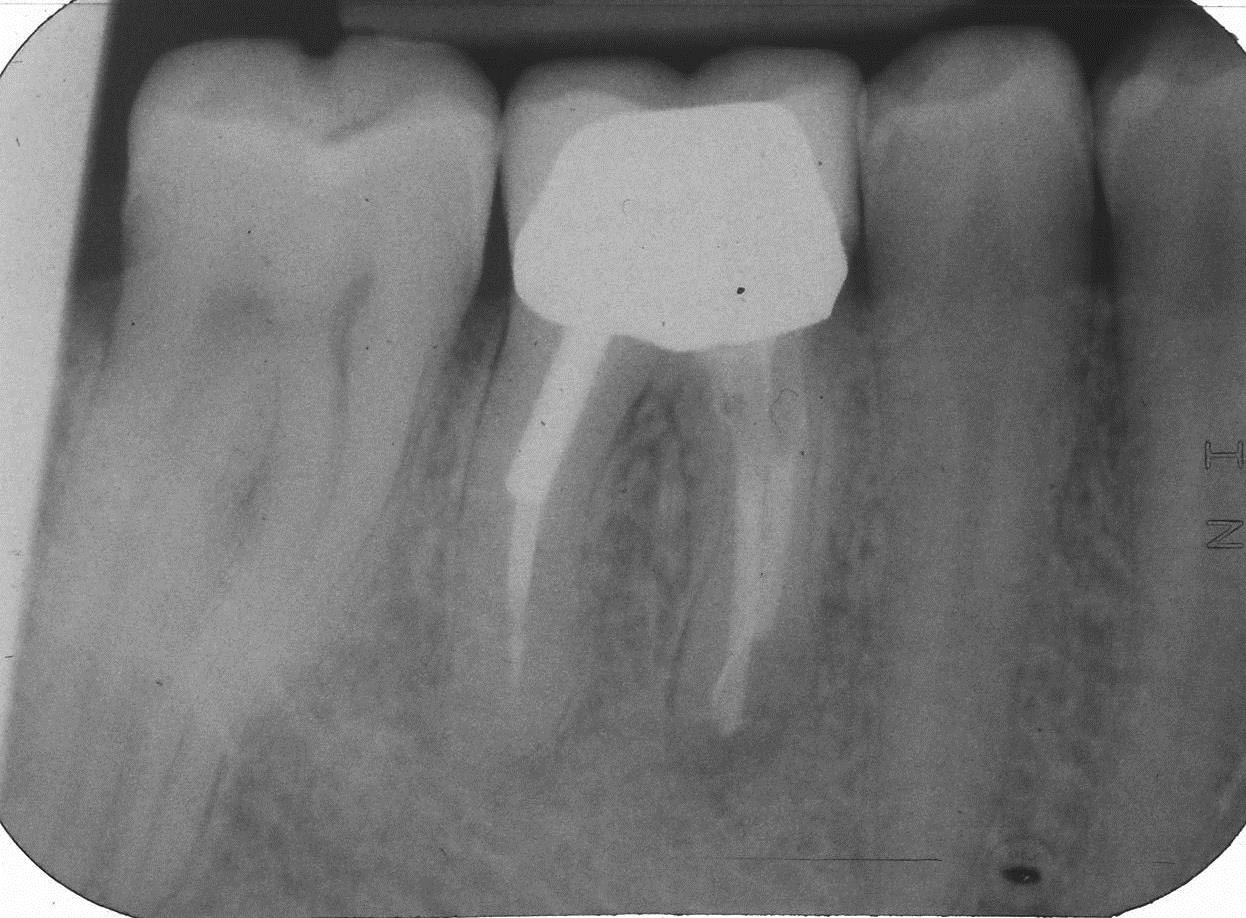

5 Kontrolle 1 Jahr nach Überkronung 05.2010 Veröffentlicht 6. Oktober 2013 am 1246 × 918 in Teilrevision Zahn 46 – Wie würden Sie entscheiden?